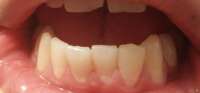

14734076948630.jpg (62Кб, 718x219)

Расскажите про расширяющие пластины. Насколько они дикцию портят? Насколько болезненно их устанавливать/носить? Есть какие-то альтернативы их установке?

Пикрилейтед мой диагноз. Прогнозируют 2-2.5 года ношения брекетов. Встанет все это в 150-200 штук. Это адекватная цена для моего случая?

> Это адекватная цена для моего случая?

Брекеты на обе челюсти + пластины, ну если ДС - думаю норм.

>ну если ДС - думаю норм.

Не, замкадск.